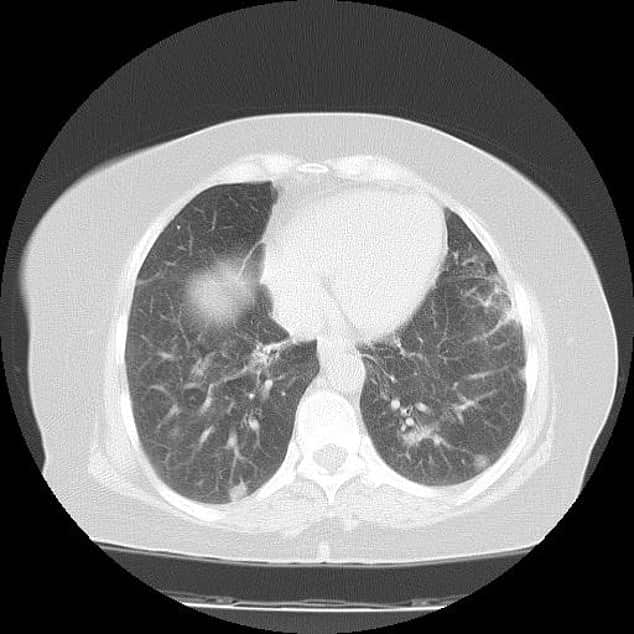

أكد المتحدث الرسمي لوزارة الصحة د. محمد العبدالعالي أن الجائحة لا تزال قائمة على المستوى العالمي، وهناك مجموعة من المناطق حول العالم تشهد ارتفاعًا في الحالات مبينًا أنه تم رُصد متحور أوميكرون في 70 دولة.

وأشار إلى أن المعلومات الأولية حول متحور أوميكرون تكمن في عدد من النقاط الرئيسة فالبيانات لا تشير إلى أنه أشد ضراوة، كما أن اللقاحات لا تفقد مفعولها ضده تحديدًا، كما أن استكمال التحصين بجرعتين لا يزال يقدم وقاية وبحمي من المرض الشديد، وكذلك الجرعة التنشيطية تضيف إلى الوقاية من المرض الشديد وتقي من الانتقال وانتشار العدوى بهذا المتحور.

وأضاف أن عدد الجرعات المعطاة في المملكة تجاوز 48 مليون جرعة، واستكمل التحصين 22 مليونًا و800 ألف شخص، وهذا المستوى يعطي المزيد من الاطمئنان ومأمونية نجني ثمارها ولله الحمد، داعيًا الجميع إلى التقيد بالاحترازات الوقائية وأن تمسك المجتمع الواعي بتلك الاحترازات المطلوبة كلها صمام أمان بعد توفيق الله، مع أهمية عدم التهاون بتلك الاحترازات وضرورة استكمال اللقاحات للوقاية من الفيروس بالإضافة إلى الحصول على الجرعة التنشيطية لتعزيز استكمال مستوى التحصين لكافة أفراد المجتمع، خاصة مع وجود المتحورات.

وأضاف د.العبدالعالي أنه تم تسجيل 51 حالة جديدة لفيروس كورونا الجديد (COVID -19) ليصبح إجمالي عدد الحالات المؤكدة في المملكة (550240) حالة، كما بلغ عدد الحالات النشطة (1910) حالات نشطة، كما بلغت الحالات الحرجة (29) حالة حرجة.

جاء ذلك خلال المؤتمر الصحفي الذي عقده اليوم الأحد، بمشاركة المتحدث الرسمي لوزارة الشؤون البلدية والقروية والإسكان سيف بن سالم السويلم مشيرًا إلى أن عدد المتعافين في المملكة ولله الحمد وصل إلى (539477) حالة بإضافة (68) حالة تعافي جديدة. كما بلغ عدد الوفيات (8853) حالة، بإضافة حالة وفاة جديدة” رحمهم الله جميعًا.